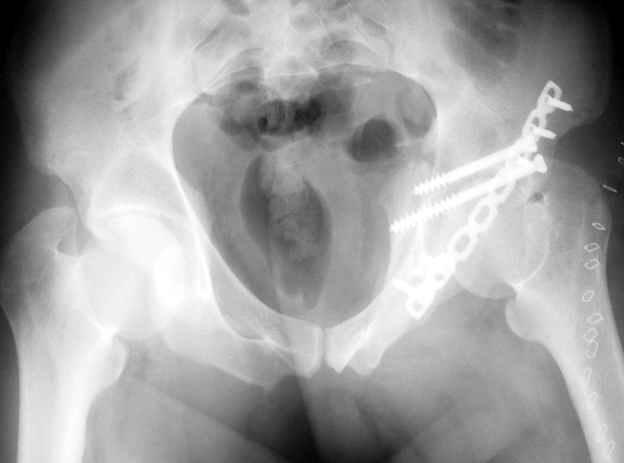

Anatoly F Lazarev 03 Сентябрь 2004, 22:39

Высылаю пример еще одного случая, остеосинтез пластиной из подвздошного доступа.

Отправитель: Djoldas Kuldjanov, M.D. 09 Сентябрь 2004, 00:43

Анатолий, во второй презентации, какой Ваш диагноз, не поперечный ли перелом ацетабулум? Вы написали, Ваш доступ был подвздошный, по моему мнению, ваш доступ лимитировал Вас к anterior column и постоянно надо было держать в контроле за натяжением femoral artery and vein, иначе грозит закупоркой артерии или вены, (были и такие experience), при сгибании в тазобедренном суставе, которое ухудшает и так ухудшенный доступ. По-моему, если доступ расширить, т.е. formal Ilioinguinal approach то применить пластину подлиннее 12-14 дырок на pelvic brim, через первое окно Ilioinguinal approach, т.е. Symphisis side, после рассечения места прекрепления muscle rectus abdominus, где достаточно места для 4 шурупов, тогда таким образом фиксированный перелом держится более стабильно и 4.5 мм шурупы для колонн можно было бы пропустить через пластину кзади впадины.

Примерно такой метод выбрал бы для моих больных.